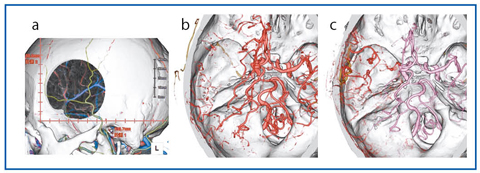

脳梗塞の場合、通常は単純CTとMRIで評価することがほとんどであるが、特にCTAでは、中大脳動脈閉塞に対する外頸動脈−中大脳動脈バイパスの手術前後の評価に用いている。術前では、外頸動脈と中大脳動脈末梢との位置関係の把握、開頭野の決定、術後では、バイパス血管の開存性評価や効果判定などを行っている(図5)。

図5 外頸動脈−中大脳動脈バイパス術

a:術前 中大脳動脈末梢と外頸動脈との位置関係の把握、開頭野の決定に利用。

b:術前 左中大脳動脈は閉塞しており末梢のみが描出されている。

c:術後 外頸動脈からのバイパスにより左中大脳動脈の血流改善が見られる。